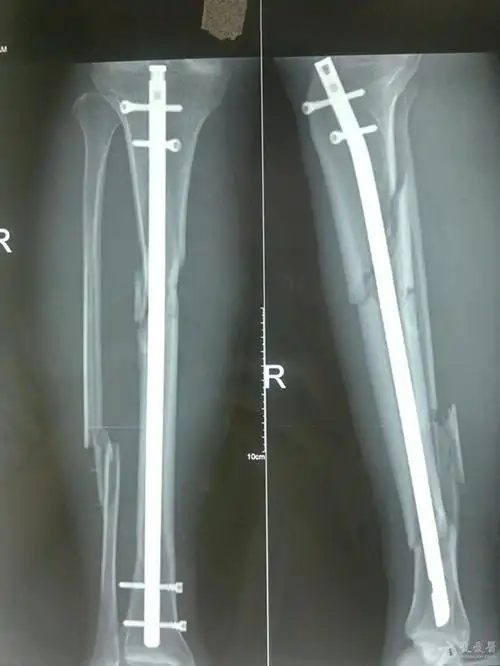

左胫腓骨粉碎性骨折

右胫腓骨粉碎性骨折行髓内钉请批评指教